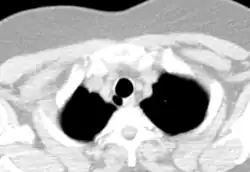

Estrutura

A traquéia de um adulto tem um diâmetro interno de cerca de 1,5 a 2 cm e um comprimento de cerca de 10 a 11 cm, mais larga nos machos do que nas fêmeas.[1] A traqueia começa na borda inferior da cartilagem cricoide da laringe[2] ao nível da sexta vértebra cervical (C6) e termina na carina,[1] o ponto onde a traqueia se ramifica nos brônquios principais esquerdo e direito, ao nível da quarta vértebra torácica (T4),[1] embora a sua posição possa mudar com a respiração.[2] A traquéia é cercada por 16 a 20 anéis de cartilagem hialina ; esses 'anéis' têm 4 milímetros de altura no adulto, incompletos e em forma de C.[1] Os ligamentos conectam os anéis.[2] O músculo traqueal conecta as extremidades dos anéis incompletos e corre ao longo da parede posterior da traqueia.[2] Além disso, a adventícia, que é a camada mais externa de tecido conjuntivo que envolve a cartilagem hialina, contribui para a capacidade da traqueia de dobrar e esticar com o movimento.[3]

Embora a traquéia seja uma estrutura da linha média, ela pode ser deslocada normalmente para a direita pelo arco aórtico.[4]